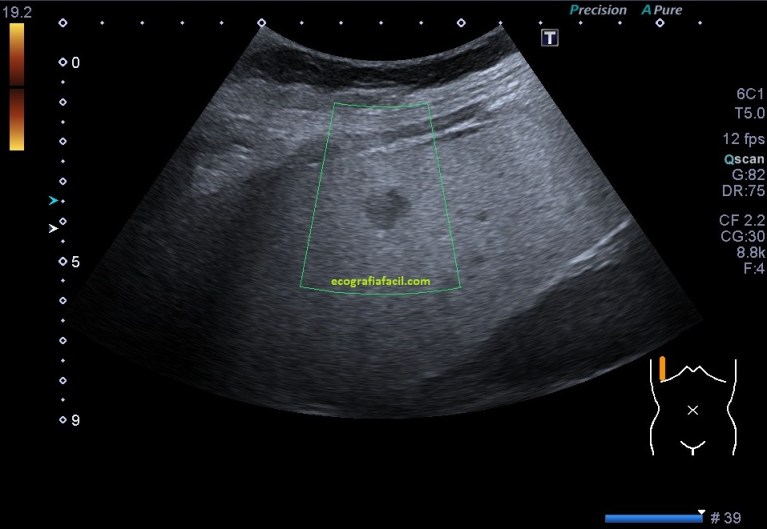

- Suelen ser lesiones solitarias, habitualmente isoecógenicas con el parénquima hepático. Formas atípicas de presentación presentan hipoecogenicidad o hiperecogenicidad.

En las imágenes puedes ver una LOE hepática que es cumple muchos criterios de los que hemos señalado arriba, pero el de la semiología, que es de los más importantes, no lo cumple. Se habla de que la HNF es una lesión isoecogénica con el parénquima hepático, ésta LOE es evidentemente hipoecogénica.

La paciente cumplía el resto de los requisitos, la edad y contestó afirmativamente cuando fue preguntada si tomaba o había tomado anticonceptivos vía oral, pero la LOE, era hipoecogénica…

La LOE fue estudiada de manera protocolaria, haciendo medidas y aplicándose el Doppler, en este caso el modo angio o doppler power.

Finalmente la Radióloga informó la lesión como HNF aún siendo marcadamente hipoecogénica, si te fijas bien en las imágenes, sobre todo en la imagen 3, donde se observa el riñón derecho, verás que existe una marcada hiperecogenicidad hepática en relación con el riñón derecho, que como muy bien sabes, deben ser isoecogénicos.

La paciente por tanto padece una esteatosis hepática, la lesión es hipoecogénica con respecto al parénquima hepático infiltrado de grasa, pero isoecogénica con el patrón ecográfico de la corteza renal, donde quiero ir a parar es a que la LOE de HNF sería isoecogénica con el parénquima hepático si eventualmente, éste, estuviese sano, es decir, si no estuviese infiltrado de grasa.